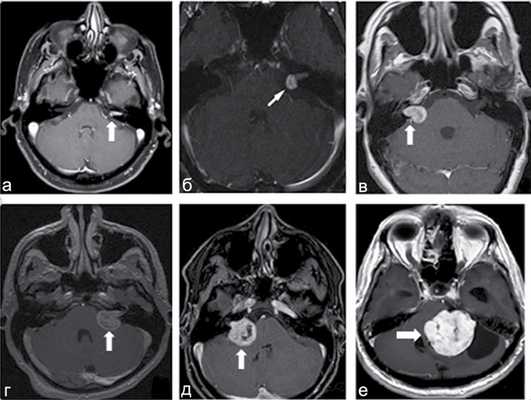

Классификация по Koos: I стадия: опухоль находится в пределах внутреннего слухового прохода, диаметр внутриканальной части составляет 1—10 мм; II стадия: опухоль вызывает расширение канала внутреннего слухового прохода и выходит в ММУ, ее диаметр составляет 11—20 мм; III стадия: опухоль распространяется до ствола головного мозга без его компрессии, диаметр составляет 21—30 мм; IV стадия: опухоль вызывает компрессию ствола головного мозга, ее диаметр более 30 мм. Ганноверская классификация по M. Samii: Т1 — интрамеатальная опухоль; Т2 — интра-экстрамеатальная опухоль; Т3а — опухоль заполняет мостомозжечковую цистерну; Т3b — опухоль распространяется до ствола головного мозга; Т4а — опухоль вызывает компрессию ствола; Т4b — опухоль грубо деформирует ствол мозга и IV желудочек (рис. 1) Рис. 1. МРТ головного мозга с контрастом. Примеры градации ВШ по Ганноверской классификации. a — Т1, интрамеатальная опухоль; б — Т2, интраэкстрамеатальная опухоль; в — Т3а, опухоль заполняет мостомозжечковую цистерну; г — Т3b, опухоль распространяется до ствола головного мозга; д — Т4а, опухоль вызывает компрессию ствола; е — Т4b, опухоль грубо деформирует ствол и IV желудочек. [7, 8].